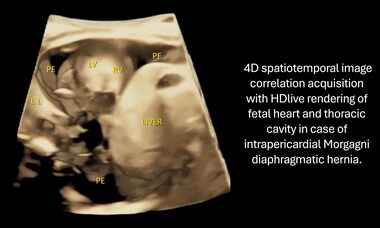

UOG Videoclip: Intrapericardial congenital diaphragmatic hernia: three-dimensional reconstruction

New UOG Journal videoclip on the usefulness of prenatal and postnatal 3D ultrasound in a case of intrapericardial Morgagni diaphragmatic hernia.